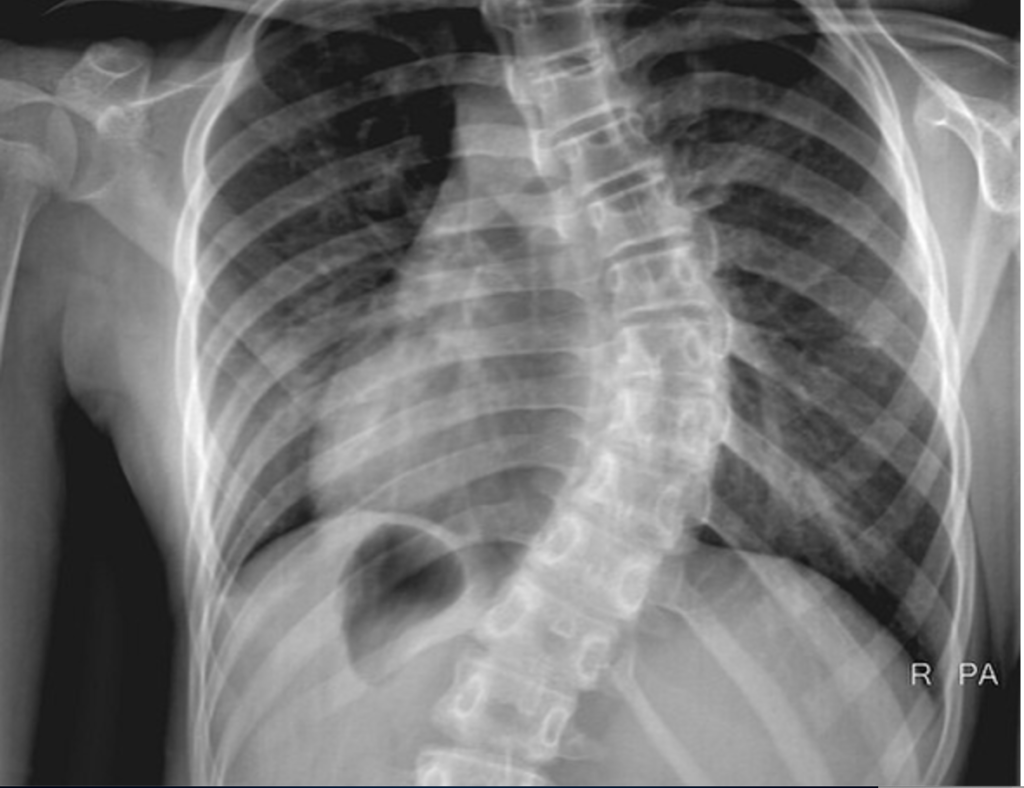

I was soon diagnosed with a 45-degree curvature and scheduled for spinal surgery at Sick Kids Hospital in Toronto under the care of the incredible Dr. Bobechko. Back in 1976, that meant a month on a Stryker Frame, stainless steel Harrington rods, and a full six months in a body cast.

Harrington Rods after Scoliosis Repair